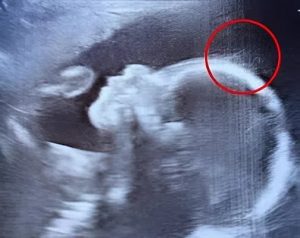

Les médecins n’en croyaient pas leurs yeux en voyant l’échographie.

« Attendez une seconde… ce sont des cheveux ? » lance-t-il, à moitié surpris, à moitié amusé. Un médecin s’approche, observe attentivement et plaisante en évoquant une future petite rock star. Sur l’image, de fins filaments semblent flotter doucement, comme des algues dans l’eau. Une vision aussi fascinante qu’inattendue.

Les professionnels expliquent ensuite à Émilie que, oui, les cheveux commencent généralement à pousser avant la naissance. Rien d’anormal à cela. Ce qui surprend tout le monde, en revanche, c’est leur longueur et leur visibilité à l’écran, bien plus marquées que d’ordinaire.